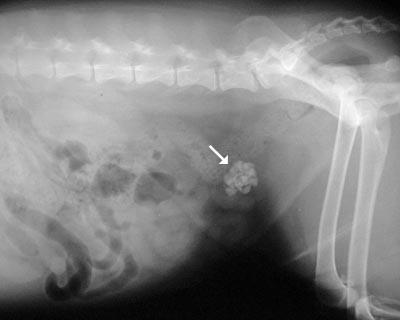

Diagnosis:thoracicradiographs;skinbiopsies –apoptotickeratinocyteswithlymphocyte satelitosis;ruleoutinfections,ectoparasites (Cheyletiella)